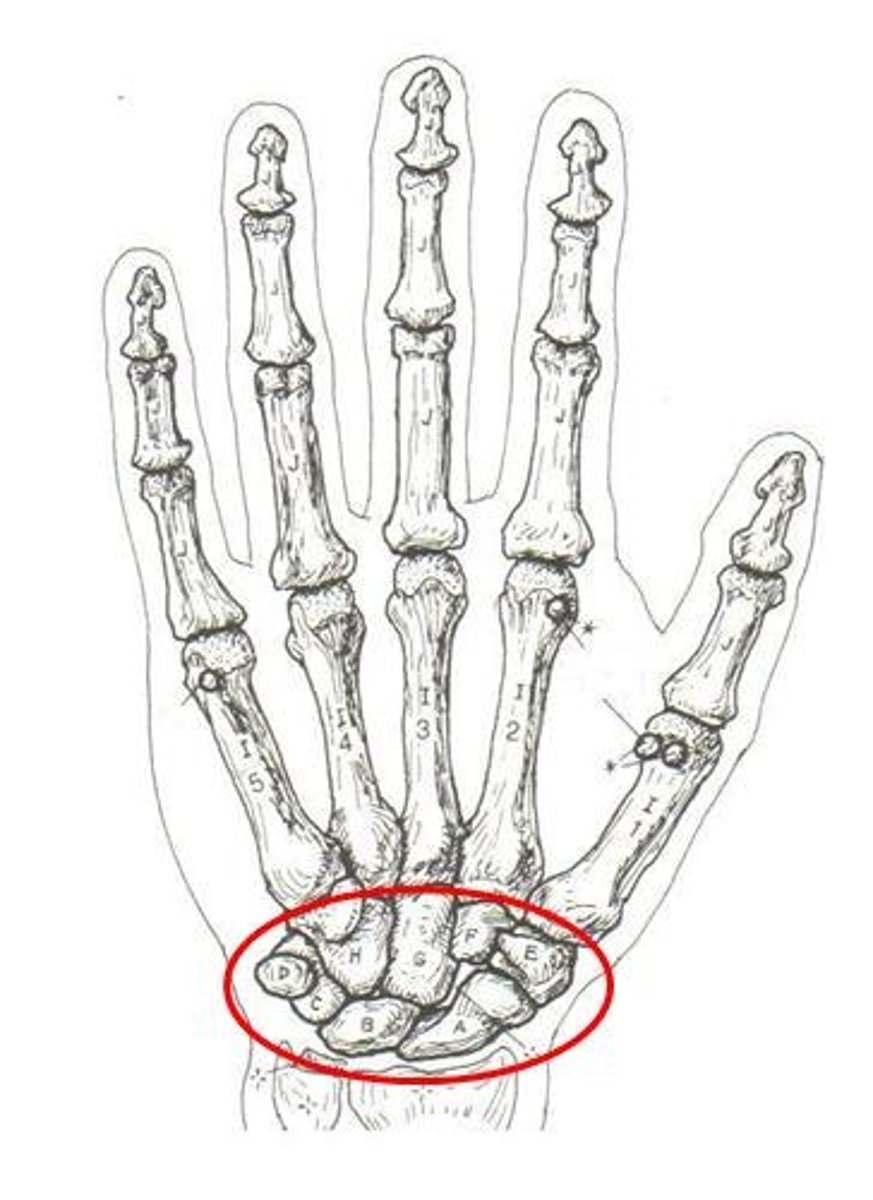

carpals

ID group

hamate

ID bone

lunate

ID bone

scaphoid

ID bone

trapezium

ID bone

carpals

ID PURPLE bones

lunate

ID specific bone

scaphoid

ID specific bone

pisiform

ID specific bone

triquetrum

ID specific bone

trapezium

ID specific bone

capitate

ID specific bone

hamate

ID specific bone